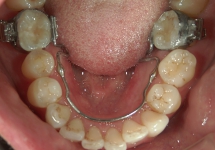

リンガルアーチ

主に奥歯の6番目の傾斜を立てなおしたり、ねじれた歯をもとに戻す際に使用する装置です。この症例の場合、舌側へ傾斜していた大臼歯が、装置の力で正常な位置まで起き上がりました。